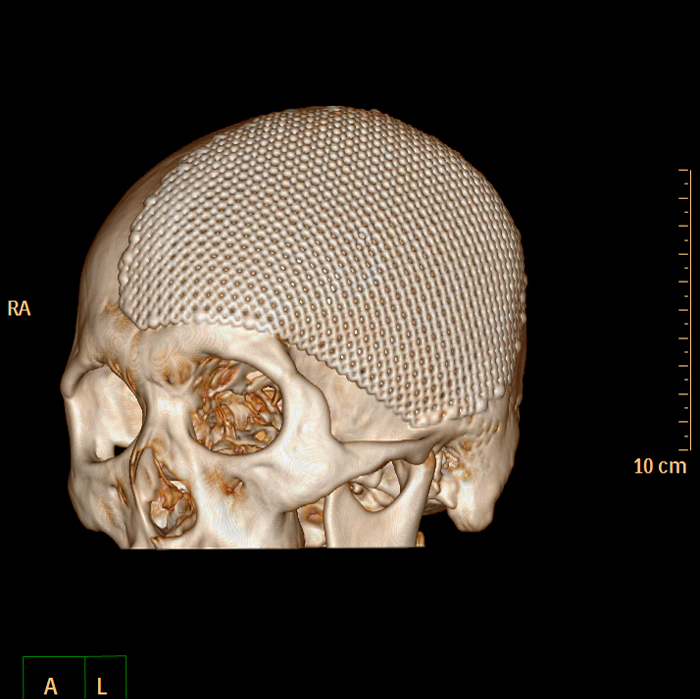

3个月过去了,小董再次来到潞河医院神经外科,由张洪兵主任牵头,组织多学科评估、讨论,认为小董的病情复杂,非常适合复合手术室进行手术,经过详细的术前讨论及术前准备,手术按计划顺利进行。首先进行脑血管造影,术中明确了硬脑膜动静脉瘘残留位置。随后张洪兵主任带领团队成员应用显微技术成功切除了残余的血管畸形,术中造影证实切除完全,同期成功钛网修补颅骨。经过两次完美的治疗,小董顺利出院。现在小董恢复很好,已回归社会,开始正常的工作生活。

修补后